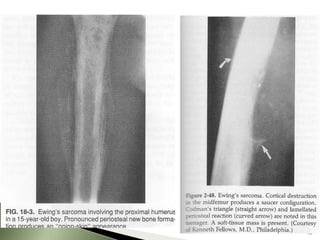

 X-RAY

◦ Moth eaten lesion

◦ Lytic or mixed lytic-sclerotic areas

present

◦ Multi-Layered sub periosteal reaction

(onion skinning)

◦ Lifting of periosteum (Codman's

triangle)